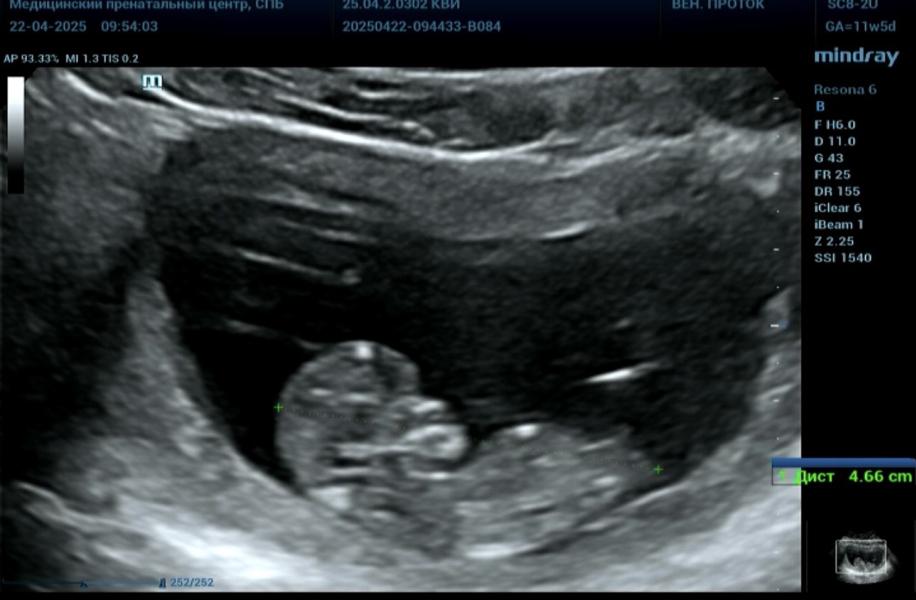

Девочки, всем привет) 1 скрининг пройден🌷Врач сказала, что на этой недели все похоже на девочек🙊А вы тут видите половой бугорок? И на кого похож?

По бугорку похоже на девочку,у мальчиков он более вверх торчит